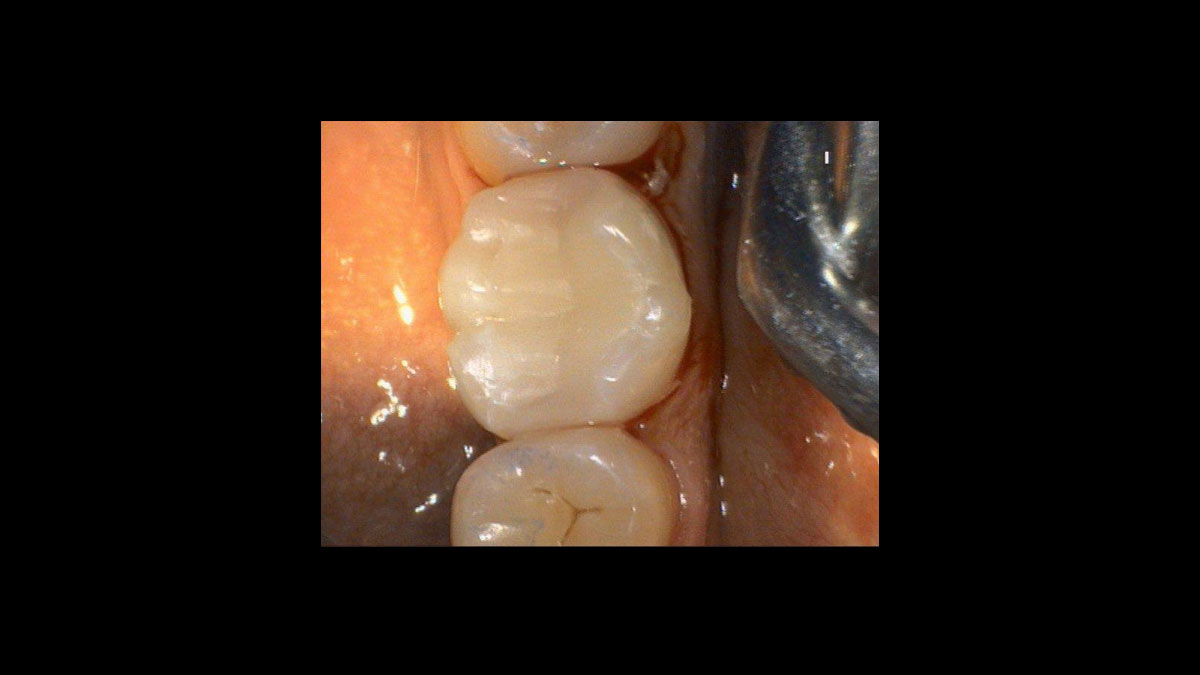

Preparación del tejido gingival antes de la toma de impresiones dentales